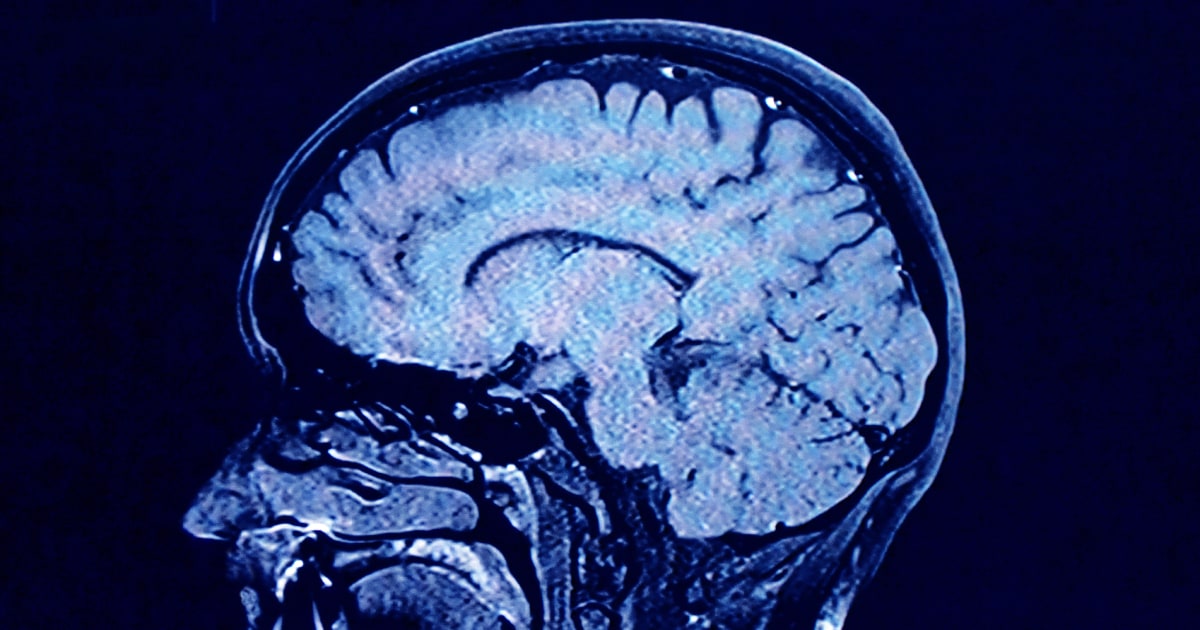

During each of these phases, our brains show markedly different characteristics in brain architecture, according to the new findings.

As we age, the human brain rewires itself. The process happens in distinct phases, or “epochs,” according to new research, as the structure of our neural networks changes and our brains reconfigure how we think and process information.

For the first time, scientists say they’ve identified four distinct turning points between those phases in an average brain: at ages 9, 32, 66 and 83. During each epoch between those years, our brains show markedly different characteristics in brain architecture, they say.

The findings, published Tuesday in the journal Nature Communications, suggest that human cognition does not simply increase with age until a peak, then decline. In fact, the phase from ages 9 to 32 is the only time in life when our neural networks are becoming increasingly efficient, according to the research.

During the adulthood phase, from 32 to 66, the average person’s brain architecture essentially stabilizes without major changes, at a time when researchers think people are generally plateauing in intelligence and personality.

Then, from 66 to age of 83, the brain tends toward “modularity,” where the neural network is divided into highly connected subnetworks with less central integration. At age 83, connectivity declines further.